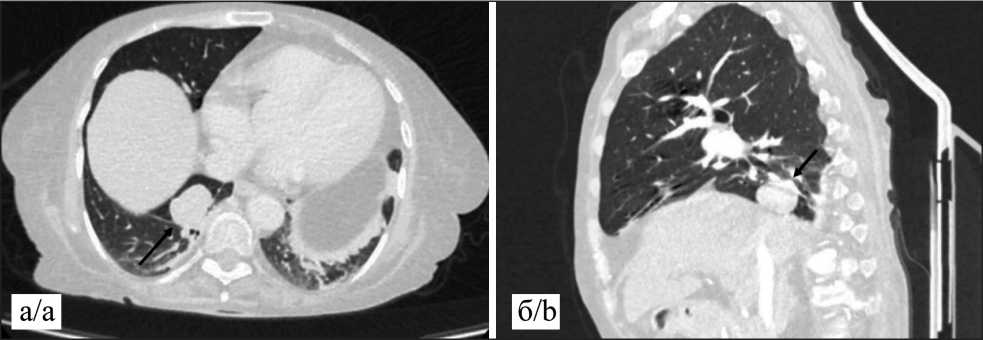

Для выявления источника патологической секреции АКТГ выполнены МРТ головного мозга с контрастным усилением и КТ грудной клетки и брюшной полости с контрастным усилением. Изменений в гипофизе и надпочечниках не обнаружено. Единственной выявленной опухолевой патологией явилось периферическое образование нижней доли правого легкого (рис. 1).

Рис. 1 Компьютерная томография в аксиальной (а) и сагиттальной (б) проекции в легочном и мягкотканом окне, толщина срезов 1,5 мм. В S10 правого легкого паравертебрально солидное периферическое образование с четкими контурами, размерами 32×26×20 мм, с высоким градиентом накопления контраста с 35 до 150 ед HU в артериальную фазу. Данных за внутригрудное лимфогенное или отдаленное метастазирование не выявлено. Примечание: рисунок выполнен авторами

Fig. 1. Axial (a) and sagittal (b) computed tomography scans with lung and soft tissue windows, slice thickness of 1.5 mm. In S10 of the right lung, there is a paraventricular solid peripheral lesion with clear contours, measuring 32×26×20 mm, with a high contrast accumulation gradient from 35 to 150 HU in the arterial phase. No evidence of intrathoracic lymphatic or distant metastasis was detected. Note: created by the authors